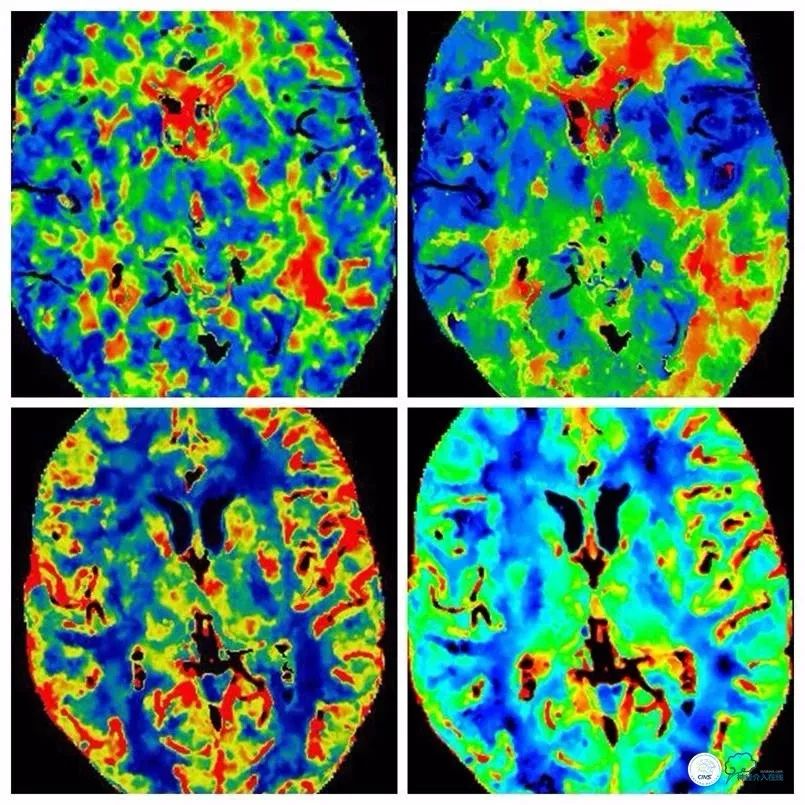

头颅CTP:左颈内动脉供血区低灌注(图3)。

图3

术后CTP:灌注较术前明显改善(图15)。

图15

术后TCD:左颈内动脉C7段流速最高达220cm/s,探及乐音,较术前明显改善,远端阻力指数在正常范围。左大脑中动脉远端流速较术前明显改善,深度49mm处血流速110cm/s。左眼动脉部分闭塞,远端流速降低,主要为颈外动脉通过滑车动脉代偿供血,可探及双向血流。